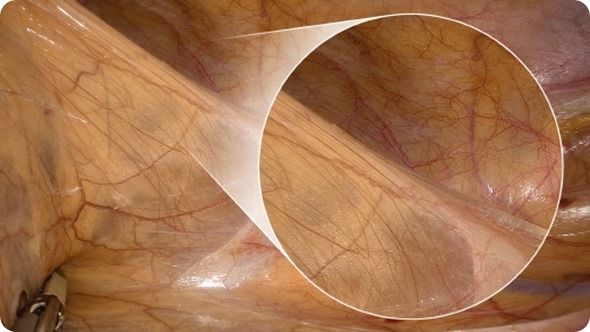

An enlarged color spectrum encompassing around one billion colors is now reality. The system improves the visibility of edges and fine details of delicate tissue, such as blood and lymphatic vessels and nerves. Above all, the richer reproduction of reds assists surgeons in ensuring that incisions are even more accurate.

The magnified visualization function allows the surgeon to use the telescope fitted to the VISERA 4K UHD even at some distance from the part of the body being operated on, while still delivering high resolution, sharp images. The remote position of the VISERA 4K UHD also prevents collisions with other handheld instruments.